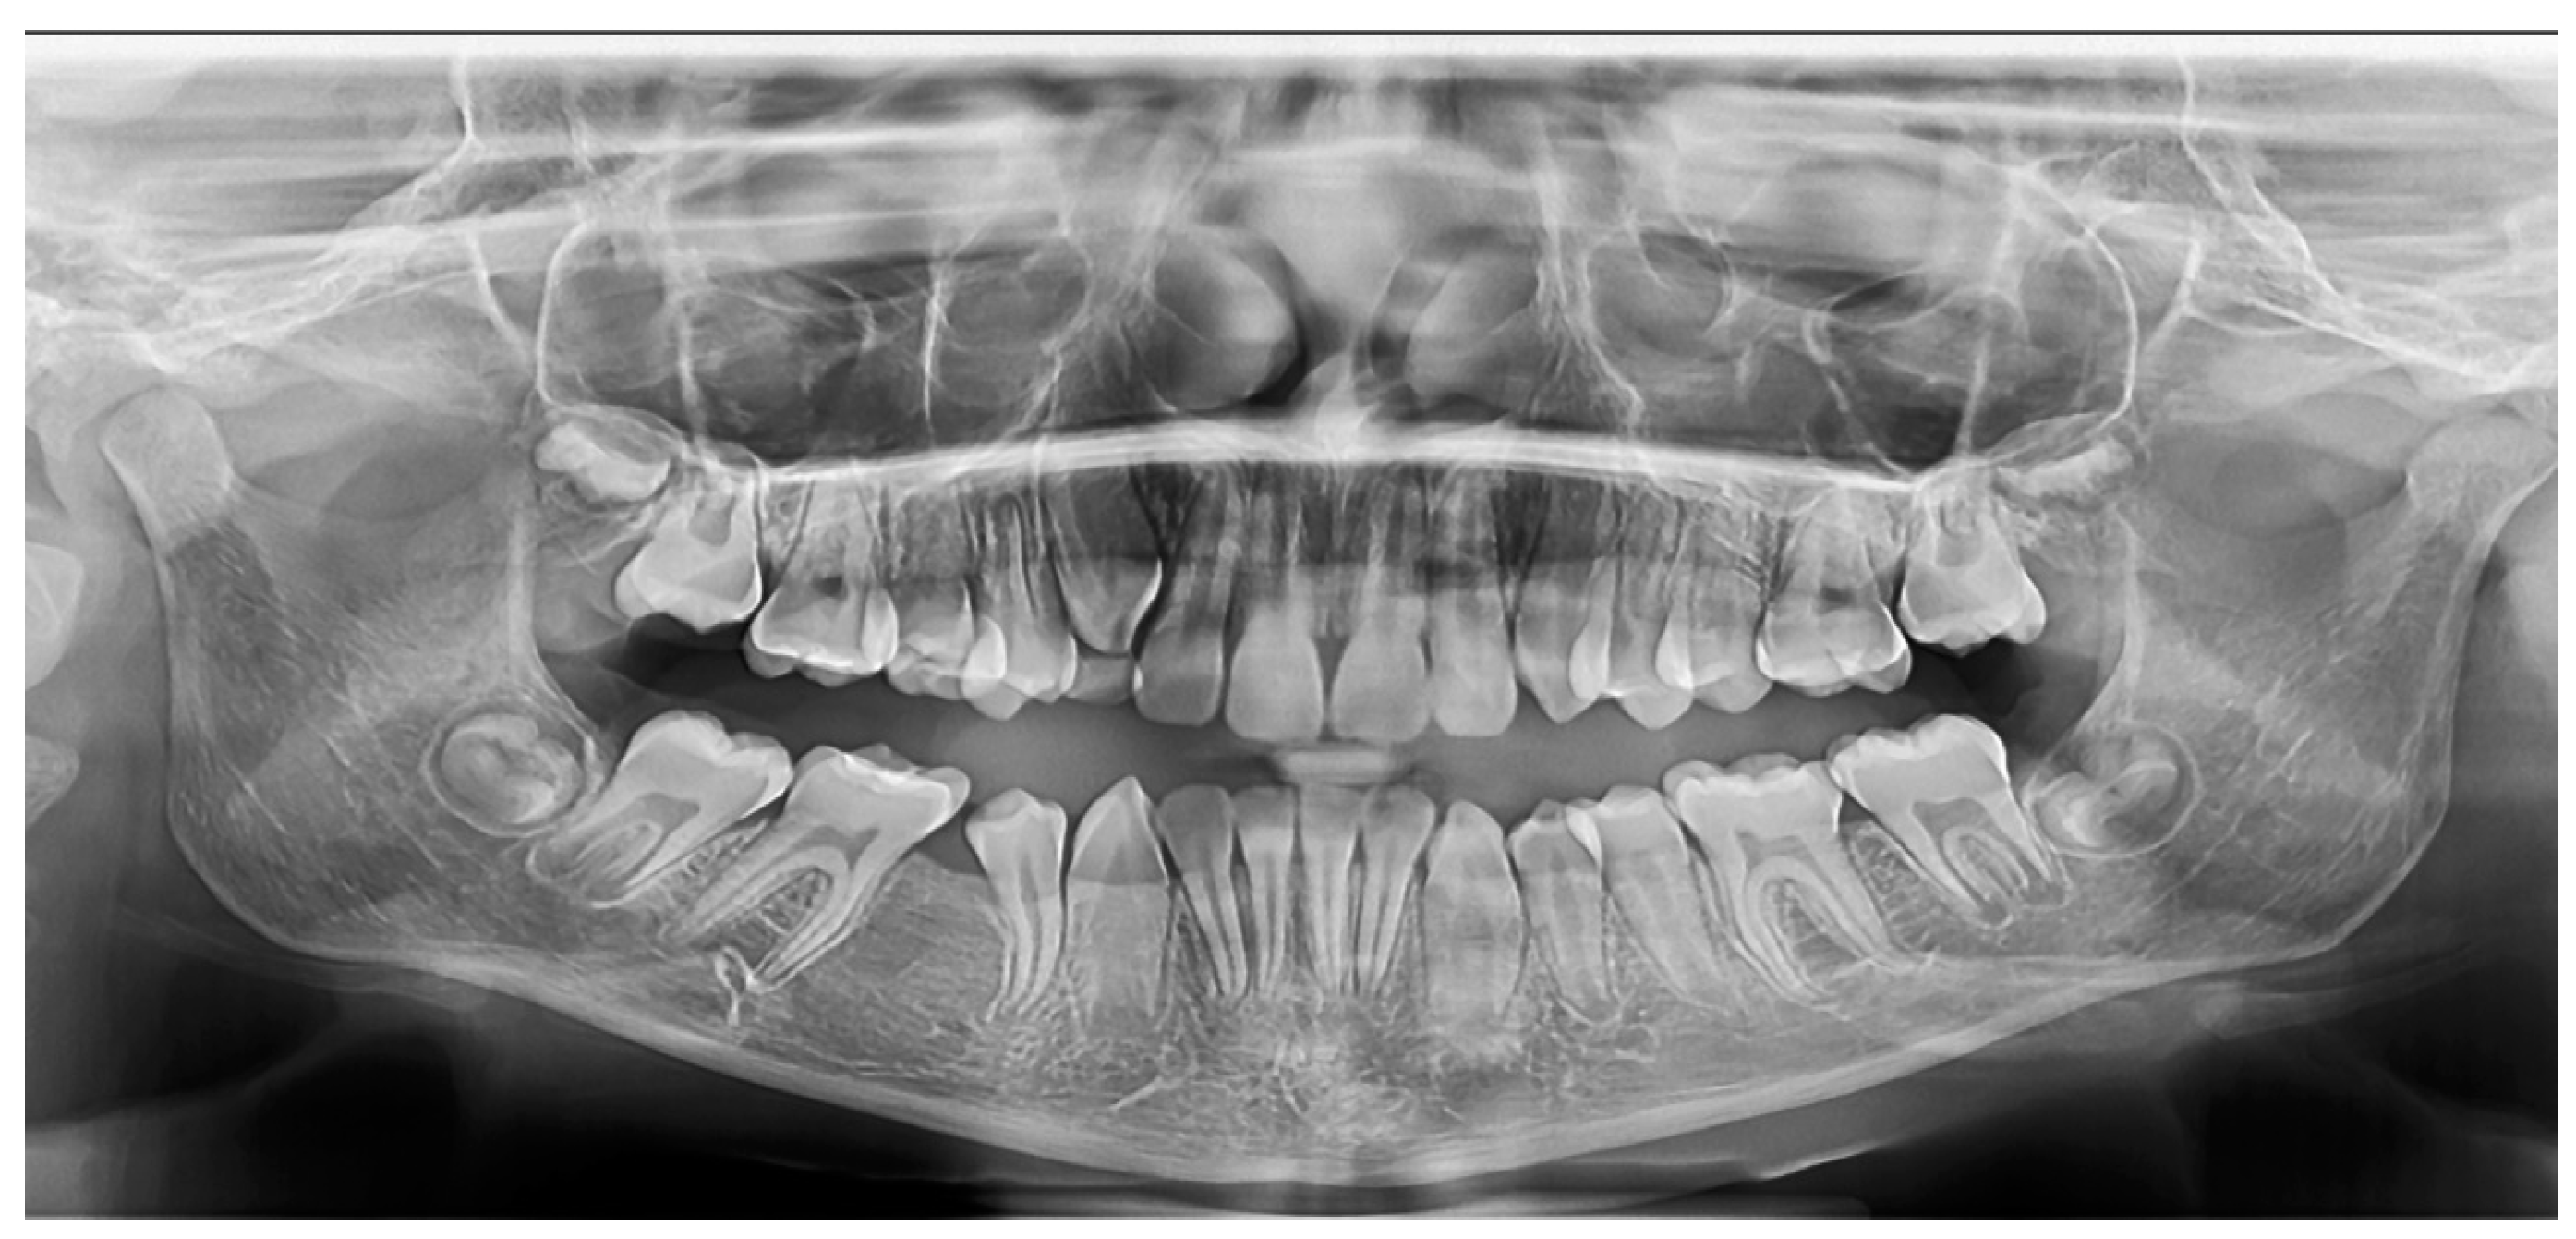

2.2.1. Case 1

2.2.2. Case 2

2.2.3. Case 3